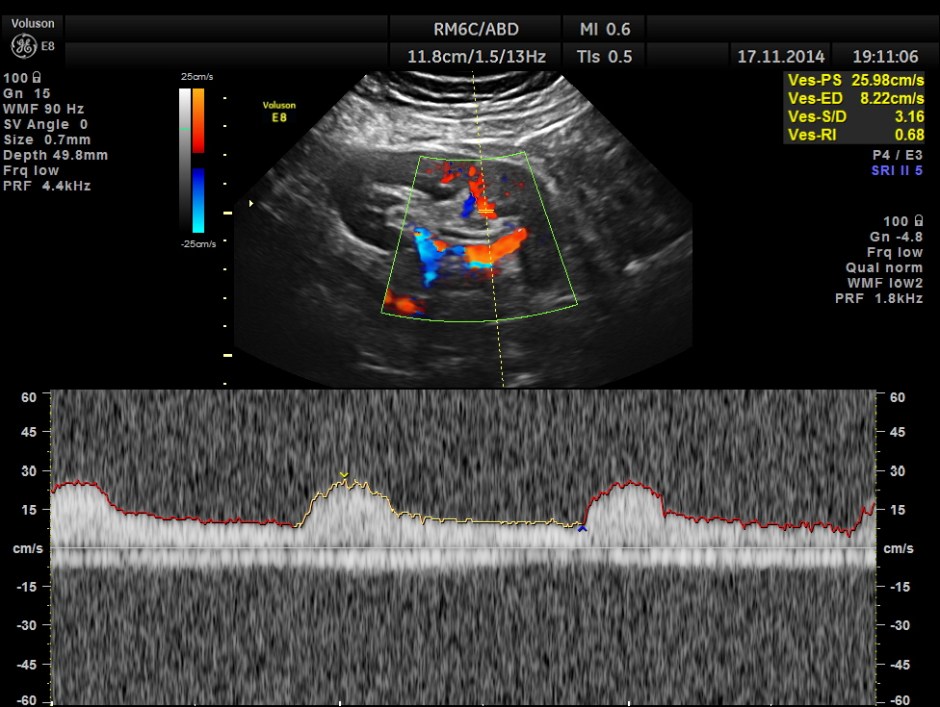

The following pictures show the transplanted kidney in the Right Iliac Fossa, with normal architecture, good Power Doppler flow and normal Spectral Doppler values.